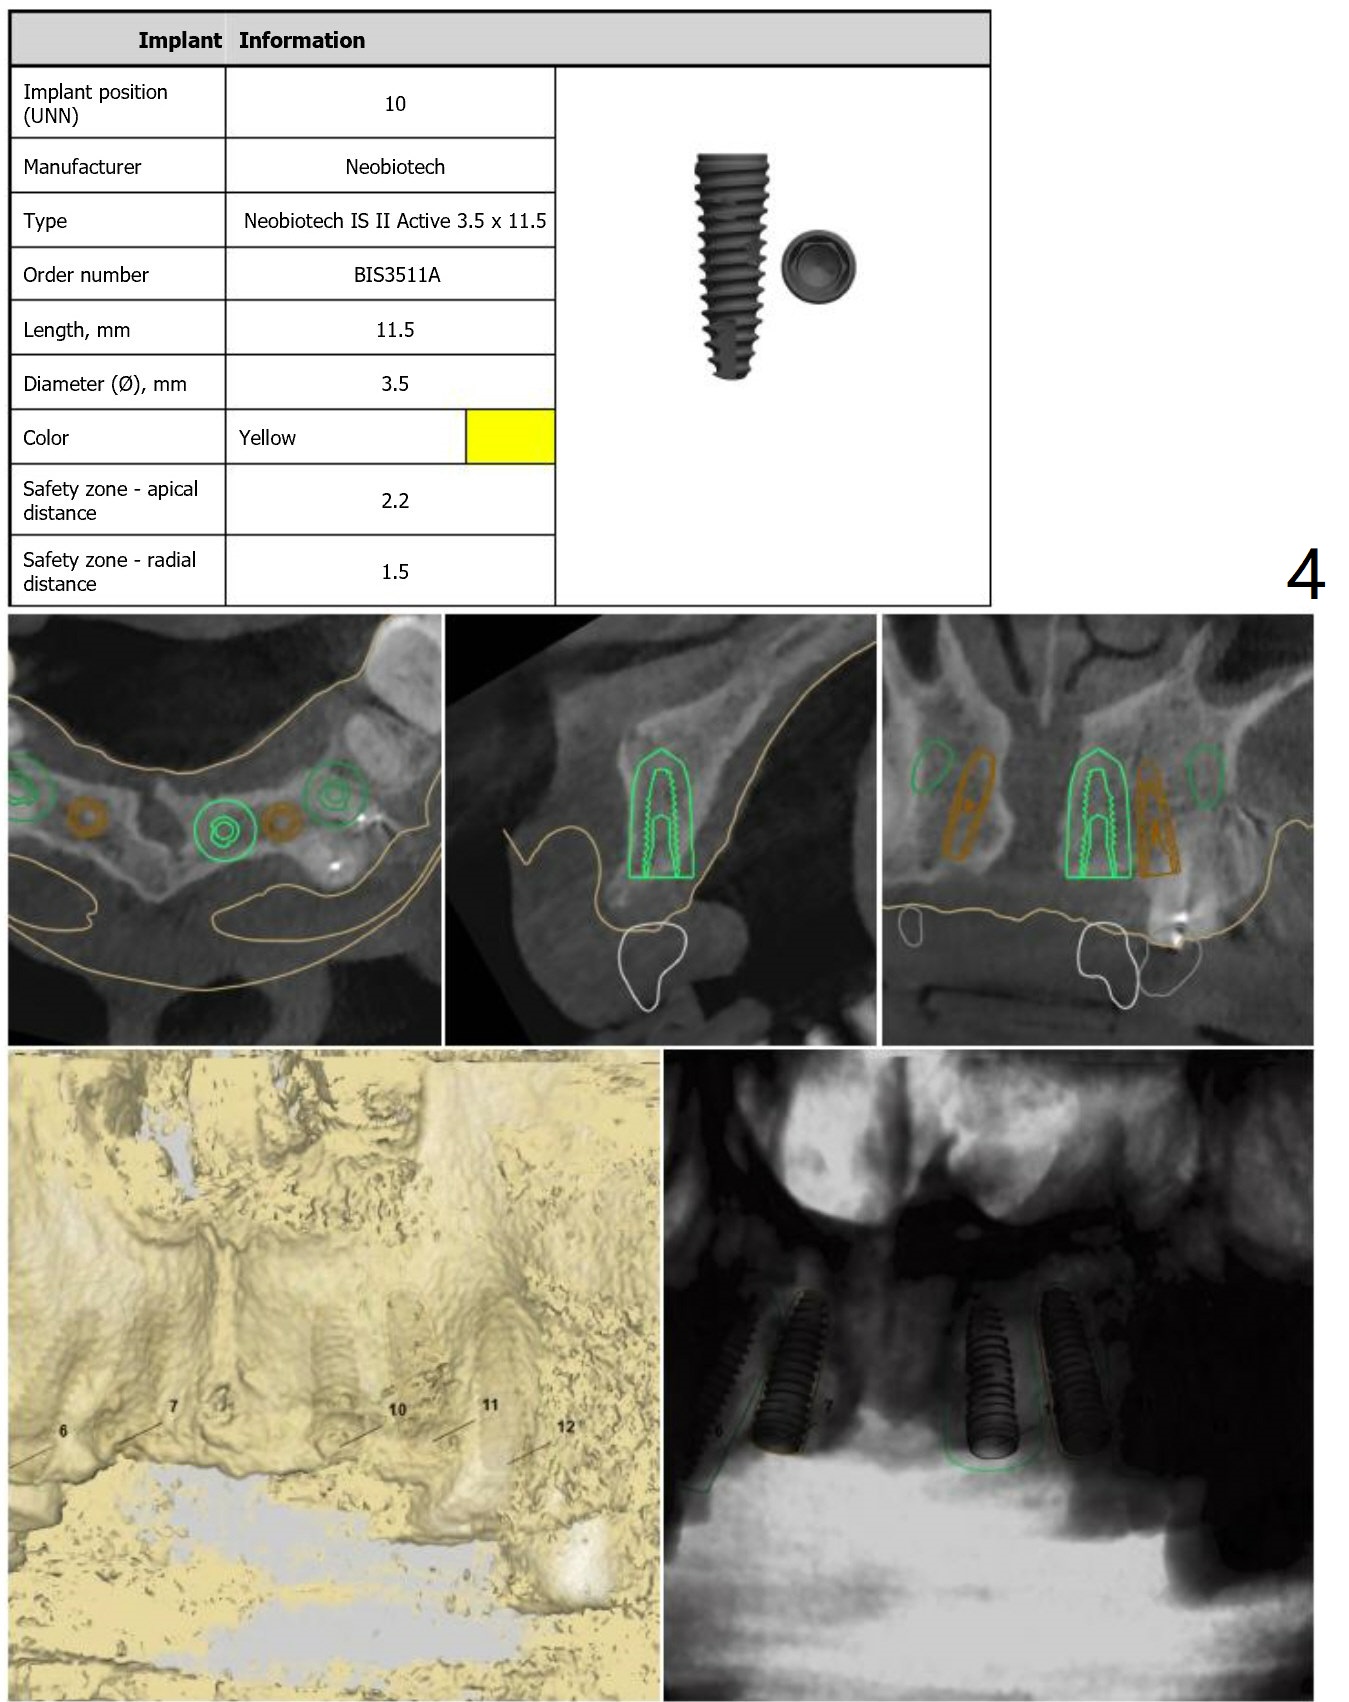

Since the apex of the tooth #5 seems to tilt mesial, implants at #6 and 7 will be placed mesial intentionally with diameters of 3.5 and 3 mm (Fig.1-3). On the left side with minor space issue, two-piece implants with 3.5 mm in diameter will be placed at #11-12 (Fig.5-6). After implant osteointegration, a 4-unit FPD will be fabricated between #7-10. Return to Upper Arch Immediate Implant, Trajectory, Metronidazole Xin Wei, DDS, PhD, MS 1st edition 11/09/2018, last revision 11/16/2018